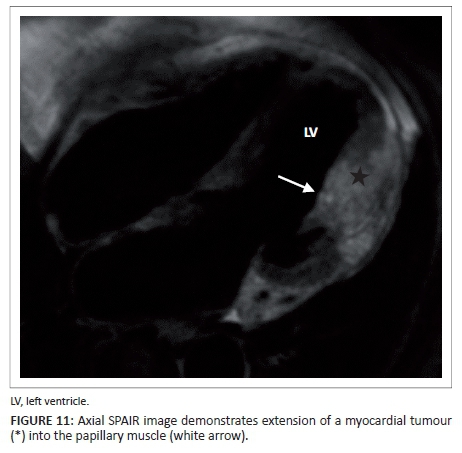

Acquired abnormalities of the papillary muscles are, however, much more common. The most common primary tumour of the papillary muscles is fibroelastoma which may be situated on the papillary muscle or on the tendinous cords. However, more common than primary tumours of the papillary muscles is the local invasion or involvement of the papillary muscles owing to direct extension of left ventricular myocardial disease, tumours (Figure 11) or ischaemic scarring.